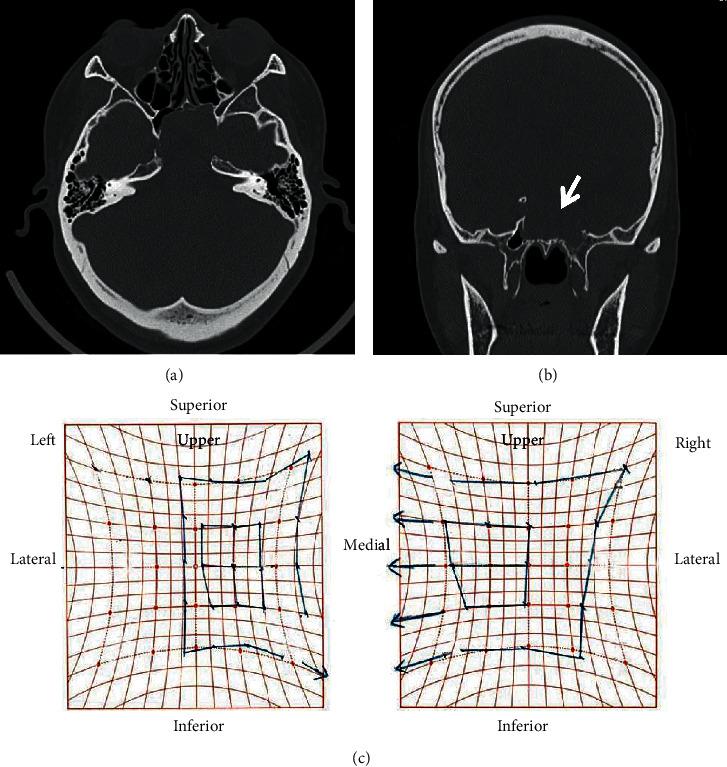

Primary solitary sphenoid sinus mucocele is rare, generally presenting with headaches or eye symptoms at the anatomical site. We report the case of a 39-year-old woman incidentally diagnosed with sphenoid sinus mucocele during a complete medical checkup. Imaging revealed that the cystic wall had developed from the rear sphenoid sinus and had spread expansively to diminish the clivus; however, no symptoms were reported, and the patient was managed with close observation. During the follow-up period, diplopia developed suddenly due to isolated left-sided abducens nerve paralysis. An endoscopic endonasal approach was used to open the frontal cystic wall, and fascia lata and fat were used for cranial base reinforcement to avoid future cerebrospinal fluid leakage, resulting in improvement during the early stages of follow-up. Treatment options for sphenoid sinus mucoceles include close observation or surgery. In our case, we chose surgery because of an acute symptomatic manifestation during observation.

原发性孤立性蝶窦黏液囊肿罕见,通常在解剖部位出现头痛或眼部症状。我们报告了一例39岁女性在全面体检时偶然诊断为蝶窦黏液囊肿的病例。影像学检查显示,囊肿壁由后蝶窦发展而来,并呈膨胀性扩展,致使斜坡骨质吸收;然而,患者并无症状报告,遂对其进行密切观察。在随访期间,患者突然因孤立性左侧展神经麻痹出现复视。采用鼻内镜经鼻入路打开额部囊肿壁,并使用阔筋膜和脂肪进行颅底加固,以避免未来脑脊液漏,在随访早期病情有所改善。蝶窦黏液囊肿的治疗选择包括密切观察或手术。在我们的病例中,由于观察期间出现急性症状表现,我们选择了手术治疗。